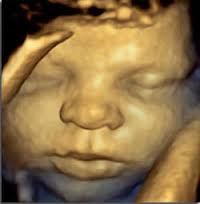

L'échographie se fait en première intention en 2D pour le dépistage. Nous utilisons également le 3D-4D dans certains cas et pour le plaisir des patientes (visualisation du visage) quand la position du fœtus le permet.